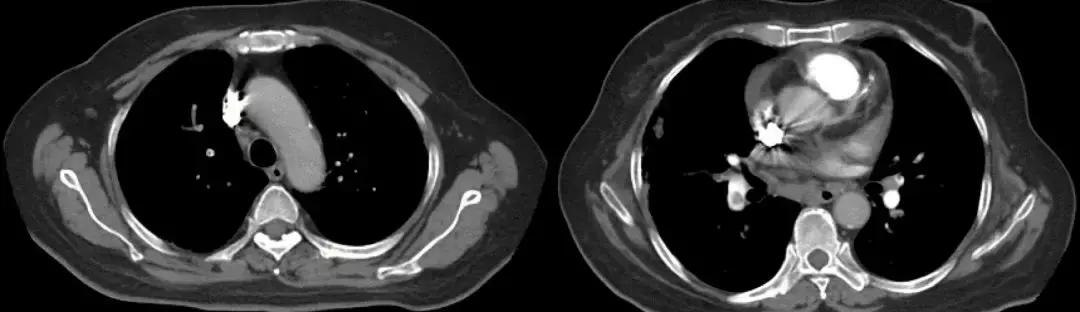

男,67岁,急性病程;发病前有旅游病史;主诉:发热、干咳伴呼吸困难2天,加重1天;查体:体温38.3℃,心率96次/分, 呼吸35次/分,血压98/63mmHg,SpO2 88%(FiO20.37),急性病容,呼吸急促,左肺呼吸音粗,右下肺呼吸音减弱,双下肺可闻及湿啰音;肺部CT示双下肺渗出、实变影,动脉血气分析提示I型呼吸衰竭。

2017-9-26

2017-9-29

支气管镜检查示

双侧气管黏膜充血,可见大量脓黄痰,左下肺基底段灌注生理盐水50ml,回收20ml,送检细菌和真菌涂片、培养;7项呼吸道病原体;EB病毒核酸、巨细胞病毒核酸;抗酸杆菌涂片及染色、结核分枝杆菌鉴定及药敏。最终结果回报:H1N1和金黄色葡萄球菌(MSSA)。降级抗生素为阿莫西林克拉维酸钾联合奥司他韦抗病毒治疗,患者症状好转出院。